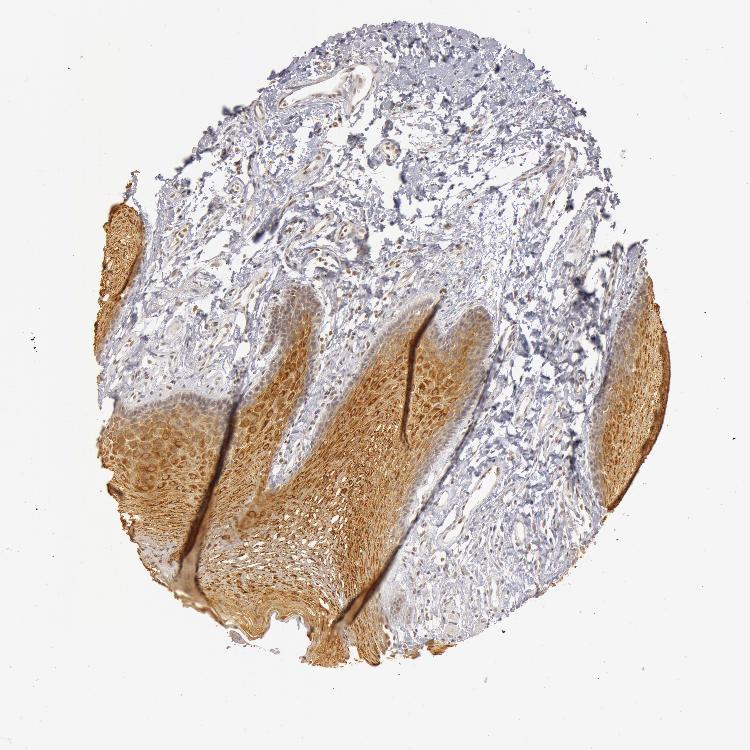

TISSUE PRIMARY DATA ORAL MUCOSA Show tissue menu

ORAL MUCOSA - Antibody stainingi

Antibody staining in the annotated cell types in the current human tissue is reported as not detected, low, medium, or high, based on conventional immunohistochemistry profiling in selected tissues. This score is based on the combination of the staining intensity and fraction of stained cells.

Each image is clickable and will lead to virtual microscopy that enables deeper exploration of all samples and also displays staining intensity scores, fraction scores and subcellular localization as well as patient and tissue information for each sample.

Antibody HPA001474

Squamous epithelial cells Medium